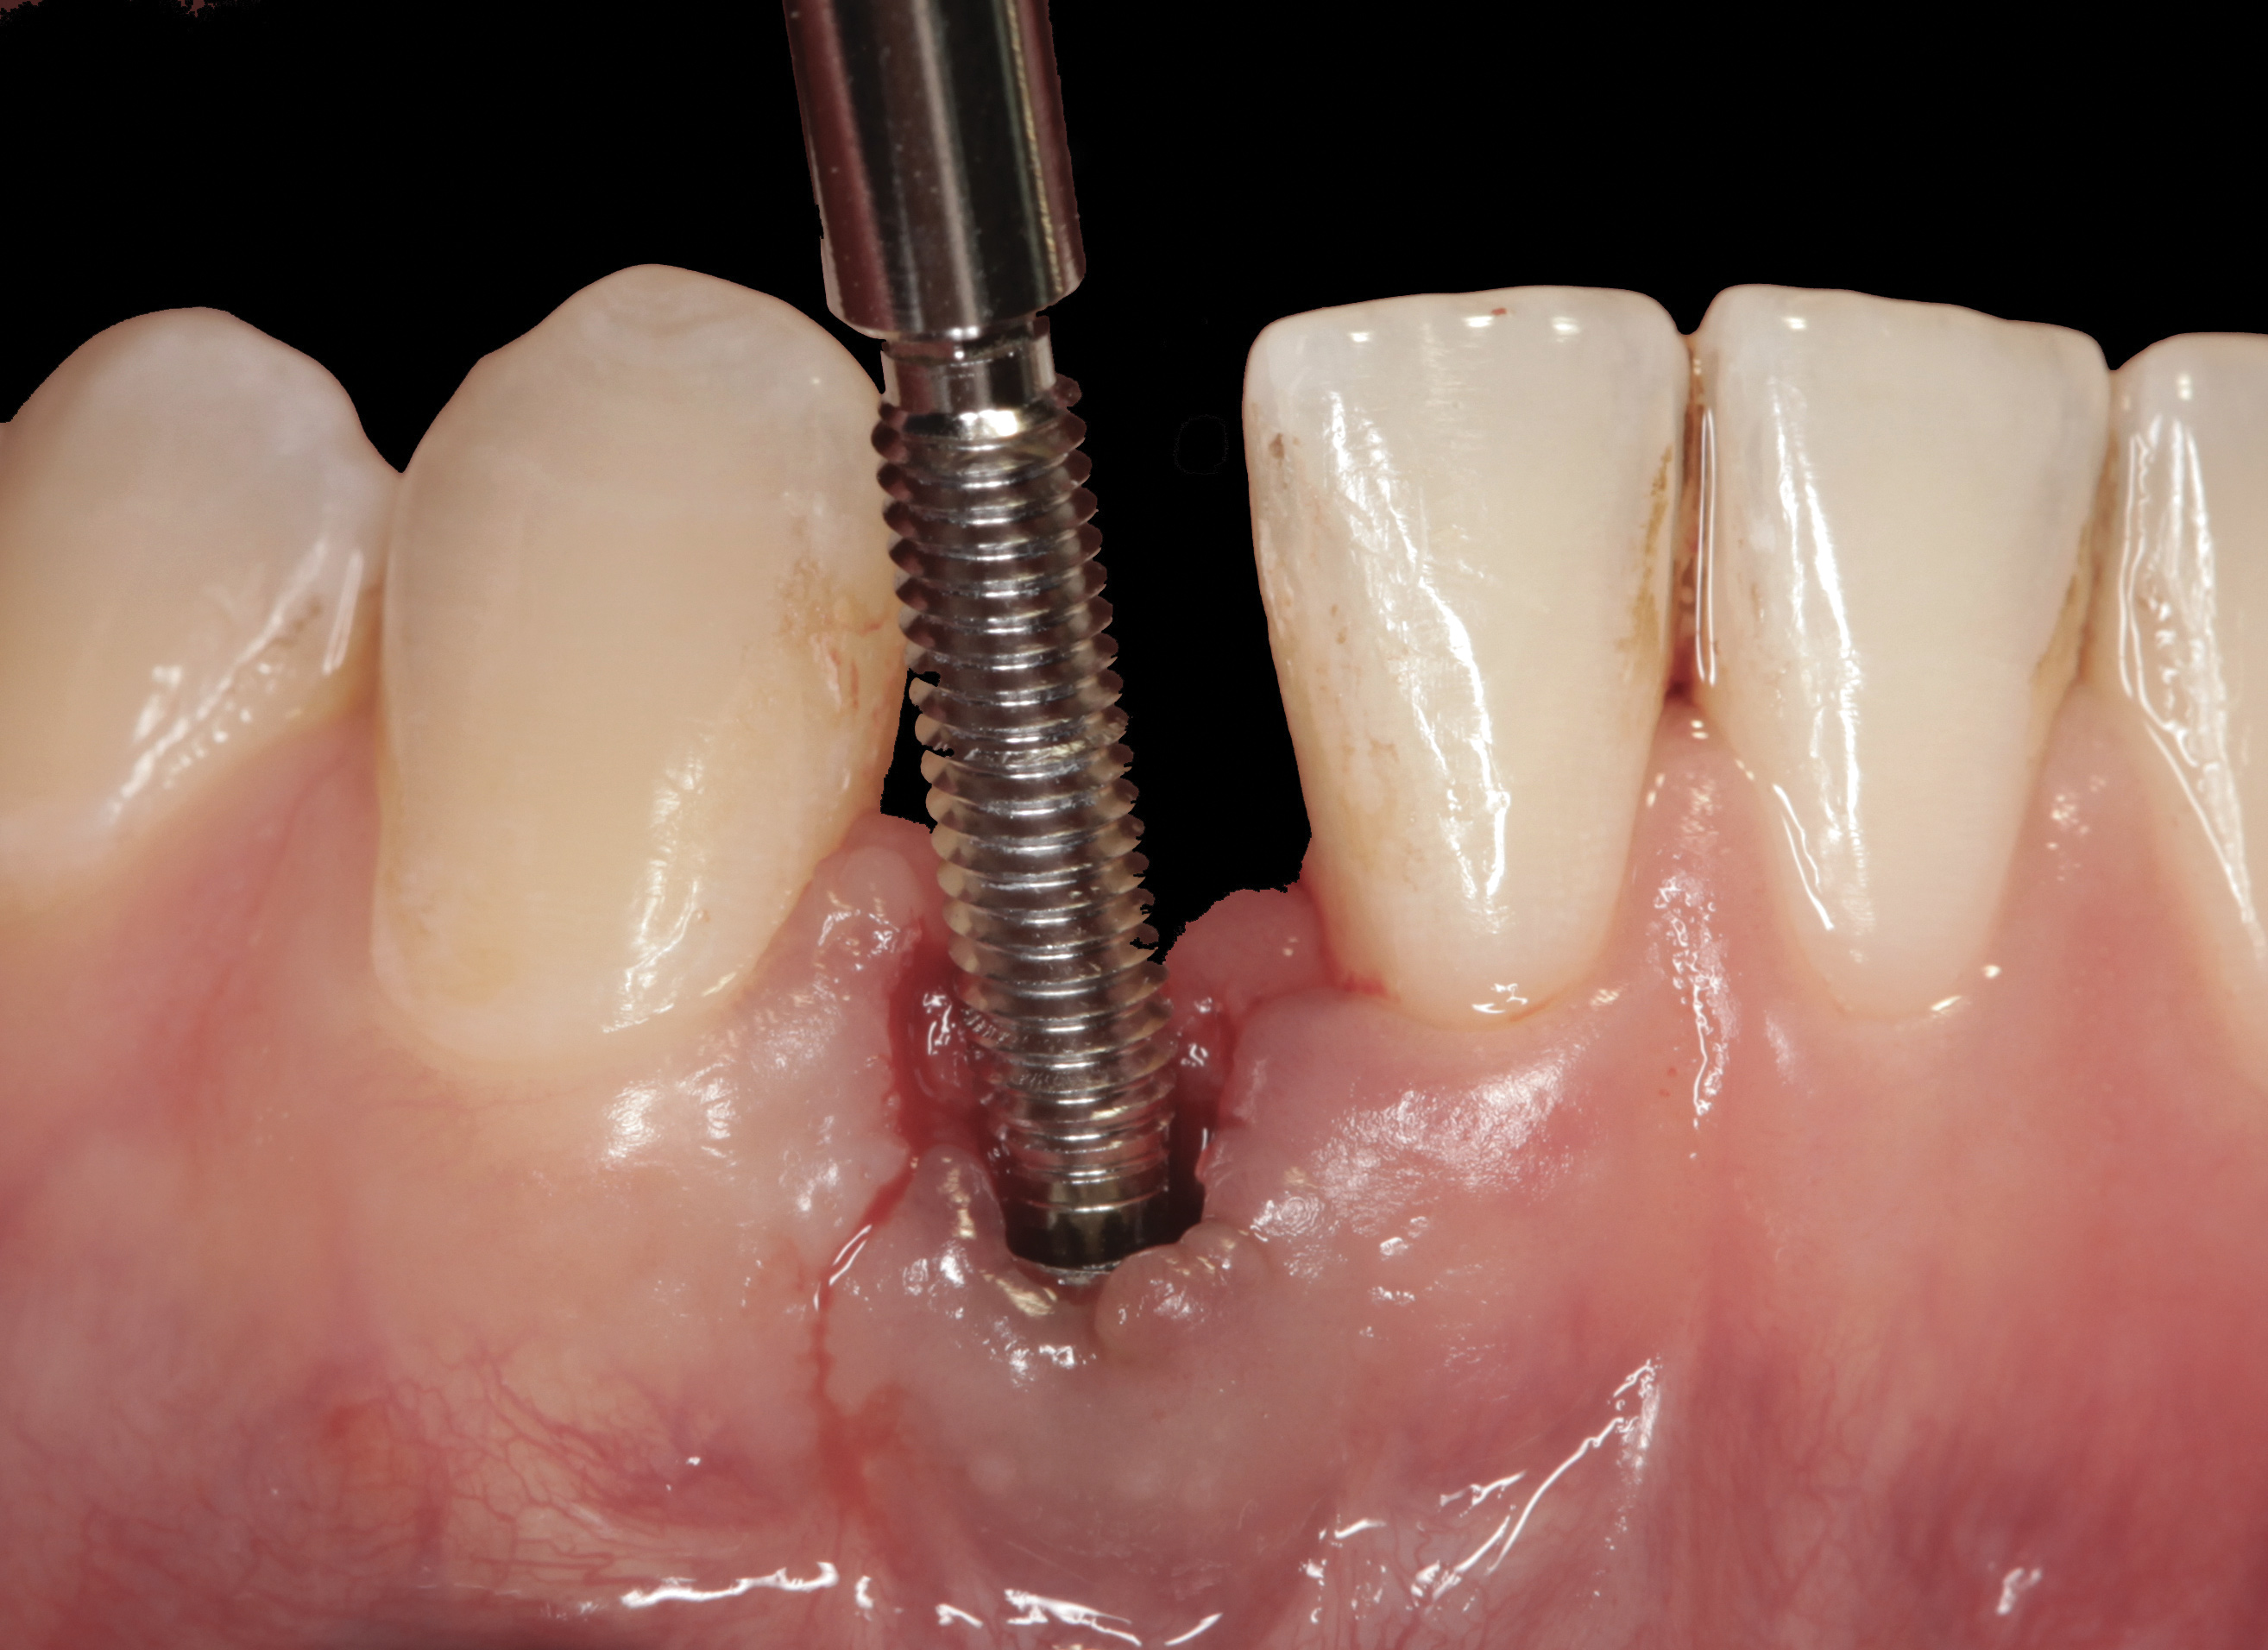

The following case report provides an example of this case scenario: A 24-year-old white male presented with congenitally missing tooth No. 26 restored with a single-tooth cement-retained implant restoration. The implant was placed excessively to the facial aspect of the edentulous site and too shallow, and the periodontal phenotype was thin scalloped (Figure 32). In an effort to mimic the lost midfacial soft tissues, pink ceramics were used as a cosmetic facade. Even though the restoration was not in the esthetic zone, the patient was highly displeased with the esthetic outcome and sought remediation.

The crown and screw-retained custom abutment were removed, and a surgical cover screw was placed into the implant, thereby allowing spontaneous gingival augmentation in situ (Figure 33 and Figure 34). Note that the lingual aspect of the implant site was significantly more coronal than the labial aspect, which was positive because the defect would be limited to a facial–lingual defect. A fixed RBR bridge was cemented on the adjacent teeth and used as a tooth-supported transitional provisional restoration (Figure 35). A few weeks were allotted to let the soft tissue heal and migrate around the cover screw (Figure 36) to see if there would be complete coverage, thereby allowing a soft-tissue augmentation procedure to be performed with primary flap closure as in clinical scenario No. 2. The major obstacle in achieving a positive tissue response was that the implant depth was also deficient because the implant–abutment connection was at the level of the free gingival margin. It was decided that the best treatment option would be to remove the implant. A high-powered reverse-torque device (Fixture Remover Kit, NeoBiotech, www.neobiotechus.com) was used to remove the implant atraumatically (Figure 38 through Figure 41). The implant socket was allowed to heal for several months not unlike an extracted tooth (Figure 42). A new implant was placed in a better position from both a restorative and esthetic perspective (Figure 43), and after a few months of healing, a new crown was made (Figure 44). A satisfactory functional and esthetic result was achieved (Figure 45 and Figure 46) without employing pink porcelain.

Fig 33. Excessive facial angulation of the implant placement shown with an abutment driver in the access screw hole.

Figure 33

Fig 34. A surgical cover screw was placed in an attempt to decoronate the implant and gain soft-tissue coverage in situ.

Figure 34